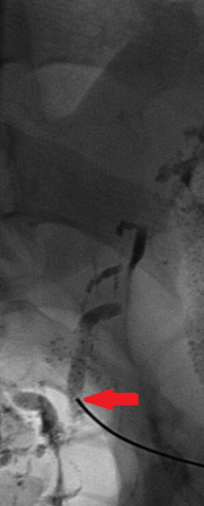

Ένας 46χρονος ασθενής , με μακροχρόνιο πρόβλημα γαστρο-οισοφαγικής παλινδρόμησης , ανθεκτικής στην συντηρητική θεραπεία , υποβλήθηκε σε λαπαροσκοπική θολοπτύχωση κατά Nissen , σε άλλο νοσοκομείο της πόλης μας . Κατά δήλωση του , η όλη διαδικασία εξελίχθηκε ομαλά και έλαβε εξιτήριο 2 ημέρες αργότερα . Μετά την παρέλευση 20ημέρου , ο ασθενής προσήλθε στο Τμήμα Επειγόντων Περιστατικών του Νοσοκομείου μας , βαριά αφυδατωμένος με κλινικά και εργαστηριακά ευρήματα νεφρικής ανεπάρκειας προνεφρικής αιτιολογίας . Από την λήψη του ιστορικού , προέκυψε πως άρχισε να βήχει επίμονα και να δυσκολεύεται στην αναπνοή τις τελευταίες 4 ημέρες. Η κλινική εξέταση ανέδειξε μεγάλη διάταση της κοιλίας συνοδευόμενη από διάχυτη ευαισθησία ενώ η αξονική τομογραφία θώρακος και κοιλίας , αποκάλυψε την παρουσία πλευριτικών συλλογών αμφοτερόπλευρα και ασκιτικού υγρού στην περιτοναική κοιλότητα . Εικόνα 1 . Αξονική Τομογραφία θώρακος – Αμφοτερόπλευρη παρουσία πλευριτικών συλλογών . ( Αρχείο κος Β . Πενόπουλος ) . Εικόνα 2 . Αξονική Τομογραφία κοιλίας . Κόκκινο βέλος – Ασκίτης . Μώβ βέλος – Σπλήνας . Πράσινο βέλος – Ήπαρ . ( Αρχείο κος Β . Πενόπουλος ) . Παρακεντήσαμε τόσο τις πλευριτικές συλλογές , όσο και τον ασκίτη και ζητήσαμε βιοχημικό έλεγχο , ο οποίος ανέδειξε υψηλά επίπεδα λευκώματος και τριγλυκεριδίων σε όλα τα δείγματα ( 154 mg/dL ) . Με το εύρημα αυτό , θέσαμε την διάγνωση του αμφοτερόπλευρου χυλοθώρακα και του χυλώδους ασκίτη . Κατόπιν τούτου , ο ασθενής διακομίστηκε στην Θωρακο-χειρουργική Κλινική , όπου τοποθετήθηκαν θωρακο-σωλήνες αμφοτερόπλευρα και παροχετεύτηκαν 1.2 λίτρα χυλώδους περιεχομένου από αμφότερες τις θωρακικές κοιλότητες . Η σίτιση από του στόματος διεκόπη και ο ασθενής έλαβε ενδοφλεβίως ολική παρεντερική διατροφή και σωματοστατίνη . Παρά την συντηρητική αγωγή , η διαρροή του χυλού συνεχίστηκε , οπότε λόγω αδυναμίας εντοπισμού του σημείου του τραυματισμού , αποφασίστηκε και εκτελέστηκε απολίνωση του θωρακικού πόρου , μεταξύ της αορτής και της αζύγου φλεβός στο επίπεδο μεταξύ 8ης και 9ης πλευράς δεξιά . Δυστυχώς , παρά την επιτυχή επέμβαση , η διαρροή συνεχίστηκε και ζητήθηκε εκ νέου η συμβολή μας στην επίλυση του προβλήματος . Μετά την μεταφορά στην κλινική μας , αποφασίσαμε και εκτελέσαμε διποδική λεμφαγγειογραφία , η οποία ανέδειξε εκτεταμένη διαρροή από τον θωρακικό πόρο στο ύψος του Τ9 και συγκέντρωση του στο αριστερό υποχόνδριο . Εικόνα 3 . Λεμφαγγειογραφία . Κόκκινο βέλος – Σημείο τραυματισμού . (Αρχείο κος Β . Πενόπουλος) . Με την συνδρομή του επεμβατικού ακτινολόγου , επετεύχθη ο καθετηριασμός του θωρακικού πόρου , κάτωθεν του σημείου της διαρροής και ο εμβολισμός με κόλλα N-butyl- cyanoacrylate . Εικόνα 4 . Καθετηριασμός θωρακικού πόρου και έγχυση κόλλας . Η παρέμβαση ήταν απολύτως επιτυχής και είχε σαν αποτέλεσμα την σταδιακή μείωση των εξερχόμενων ποσοτήτων από τις θωρακικές παροχετεύσεις όσο και της περιμέτρου της κοιλίας . Μετά την πλήρη αποστράγγιση τους , οι θωρακοσωλήνες αφαιρέθηκαν και ο ασθενής ελεύθερος συμπτωμάτων , επανήλθε στην σίτιση από του στόματος . Εξήλθε του Νοσοκομείου , λίγες ημέρες αργότερα και μετά παρέλευση 6μήνου , ήταν ελεύθερος συμπτωμάτων , σιτίζονταν ελεύθερα από του στόματος , είχε πετύχει σημαντική απώλεια βάρους , η περίμετρος της κοιλίας του είχε επανέλθει στα φυσιολογικά επίπεδα και δεν υπήρχαν ευρήματα που να συνηγορούν στην υποτροπή του χυλώδους ασκίτη .